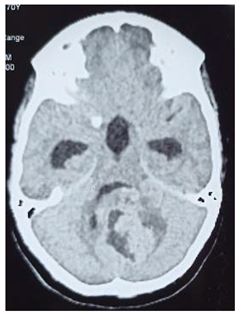

Preprints 114904 i002

Operation: After clear counseling to the family, subsequently Left fronto –tempro-parietal craniotomy was done, operative findings: very thin bone with multiple eaten parts, the dura was very thin and adherent to the over lining bone, the tumor itself was multi in components, mucus like material and solid parts and cystic part which contained yellow fluid

In closing the dura, graft from the temporalis fascia was taken and closed in water tide.

Patient was recovered from anesthesia well, taken to the ICU on nasal oxygen

In the first post operative day, the patient showed dramatic improvements in his level of conscious, free of headache. Few weeks post operative; patient came to the clinic walking and looks happy.

Histopathology

Pilocystic astrocytoma